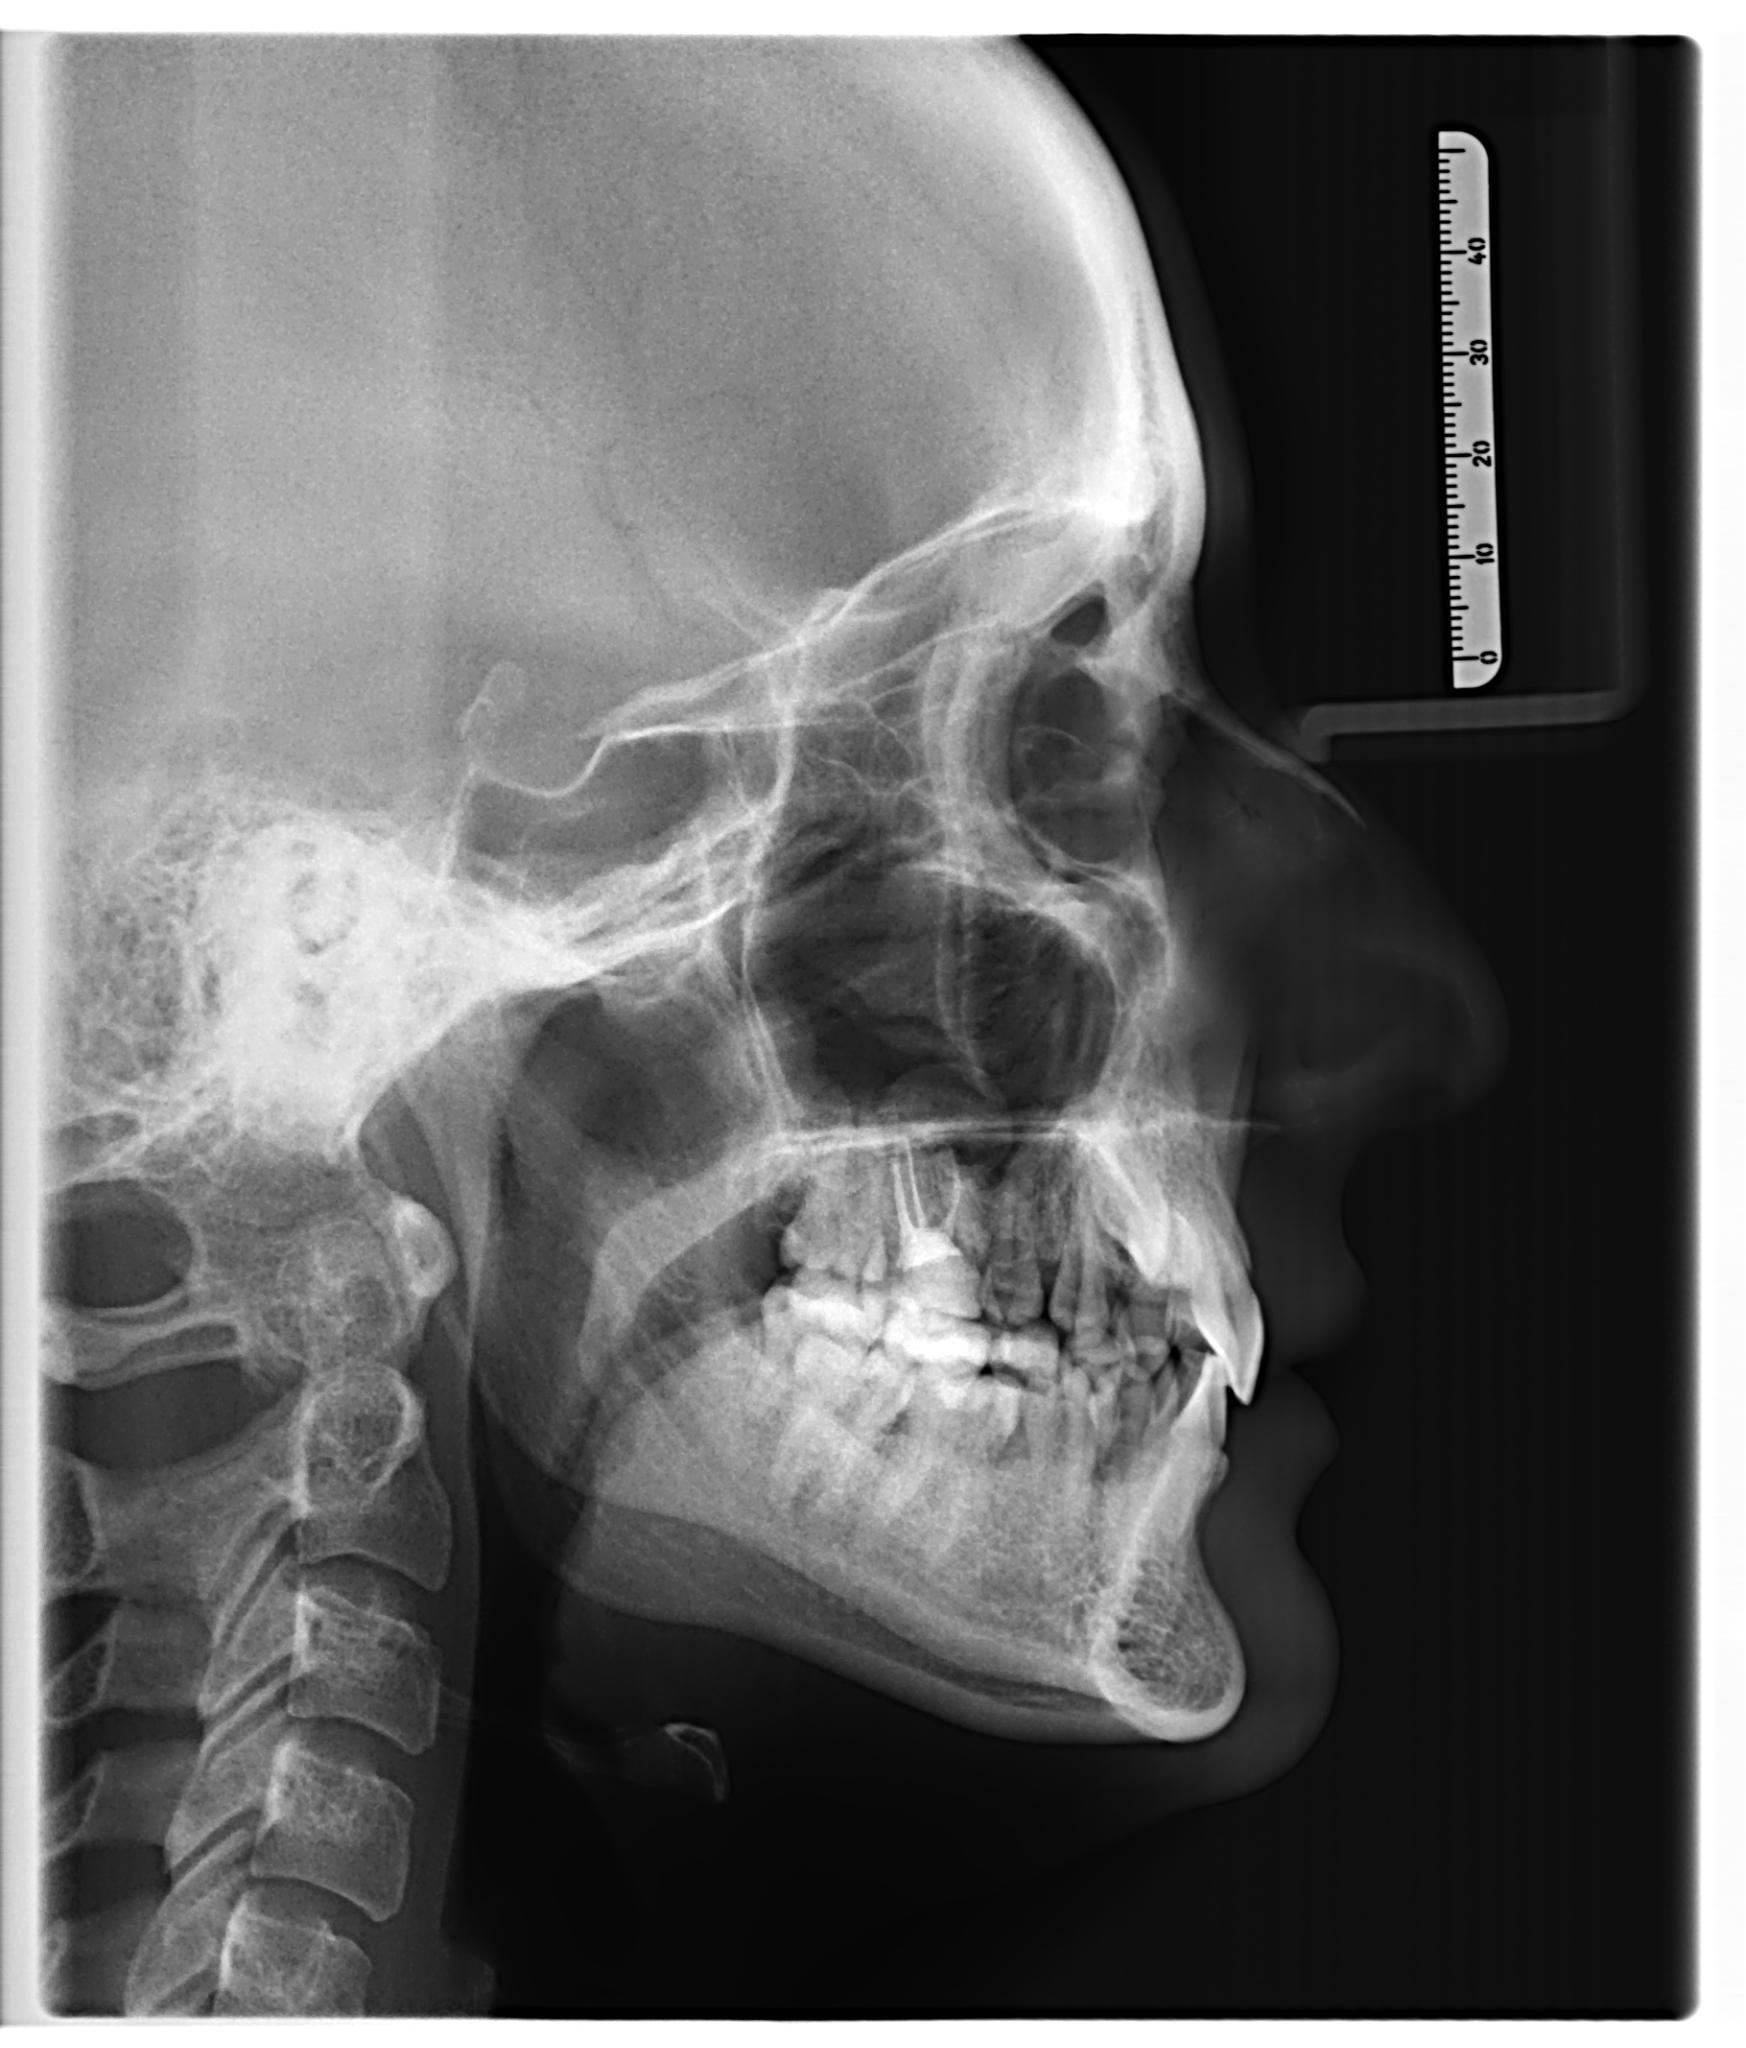

Что вы получаете в итоге? Не просто диск, распечатку или отправку на электронную почту. Вы получаете стопроцентную уверенность. Уверенность в том, что план лечения имплантации составлен идеально, что все каналы будут пройдены до конца, а «зуб мудрости» удалят аккуратно, не задев важные нервы.